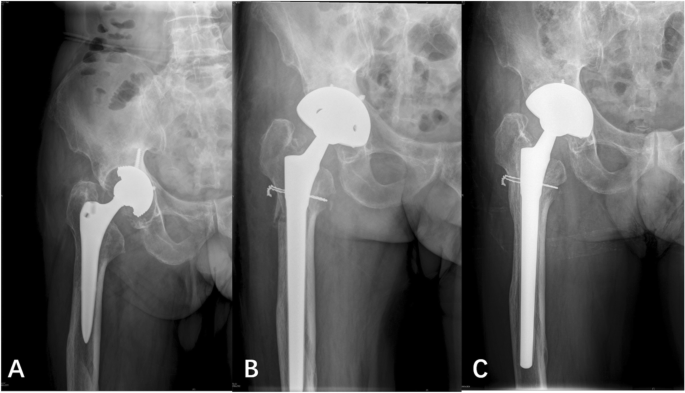

At the last follow-up, prosthesis subsidence in the cylindrical and tapered groups was 0–15 mm with an average of (4.17 ± 4.20) mm and 0–8 mm with an average of (2.17 ± 1.49) mm, respectively (Fig. 2). A significant difference was observed in prosthesis subsidence between the two groups. All prosthesis subsidence stopped within 1 year after operation. Ten hips in the tapered group (15.2%) and seven hips in the cylindrical group (13.0%) experienced subsidence of more than 5 mm (P > 0.05). Among the 10 hips in the tapered group, eight had type IIIA femoral defects, and two had type IIIB femoral defects. Among the seven hips in the cylindrical group, six hips had type IIIA femoral defects, and one had a type IIIB femoral defect.

Postoperative complications

Intraoperative fractures were found in eight cases (14.8%, Fig. 4) in the cylindrical group and three cases (4.5%, Fig. 5) in the tapered group. A significant difference was observed between the two groups (P < 0.05). In the cylindrical group, five cases had femoral trochanteric fractures (with steel wire binding), and three cases had femoral shaft fractures (with steel wire binding). All fractures were healed. In the tapered group, three cases had femoral shaft fractures (with steel wire binding), and the fractures healed after operation.